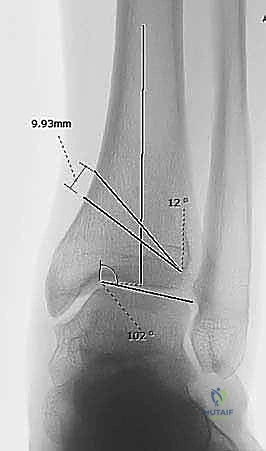

التشخيص الدقيق بالأشعة لتشوهات الكاحل

1. التخطيط الجراحي الدقيق (Pre-operative Planning)

يتم إجراء صور أشعة سينية خاصة (طويلة للساق بالكامل أثناء الوقوف) وأشعة مقطعية (CT Scan) ثلاثية الأبعاد. يقوم الدكتور محمد هطيف باستخدام برامج حاسوبية متقدمة لحساب الزاوية الدقيقة للتشوه، وتحديد حجم "الوتد العظمي" (Bone Wedge) الذي يجب إزالته أو إضافته لإصلاح المحور.